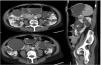

This is a 69-year-old woman with a history of hypertension, axonal sensory polyneuropathy due to Cerebellar Ataxia with Neuropathy and Vestibular Areflexia Syndrome (CANVAS) and ADPKD diagnosed at 40 years of age, with subsequent confirmation of PKD2 mutation. Throughout the course of the disease the following incidences stand out: evacuating puncture of the cysts compressing the renal artery approximately 30 years ago and several episodes of intestinal pseudo-obstruction justified by an acquired megacolon secondary to intestinal compression by the renal cysts (Fig. 1) that required the puncture and sclerosis of a large dominant cyst in the last year. Despite this, the patient continued to have difficulty swallowing and abdominal pain. At that time renal function remained normal and she did not present criteria for rapid progression, precluding the use of tolvaptan according to current indications. However, in September 2022, in agreement with the patient, we decided to trial compassionate treatment with tolvaptan, with the aim of decreasing abdominal volume, as well as better pain control. She was prescribed 45 mg of tolvaptan in the morning and 15 mg eight hours later.